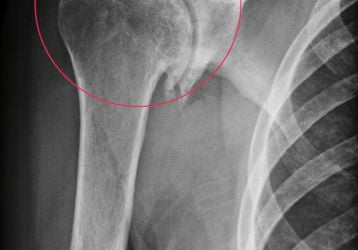

Деформирующий остеоартроз плечевого сустава: лечение 1-2-3 степени

Деформирующий остеоартроз плечевого сустава: способы диагностики, лечения и профилактики. Медикаменты, хирургия и физическая активность.